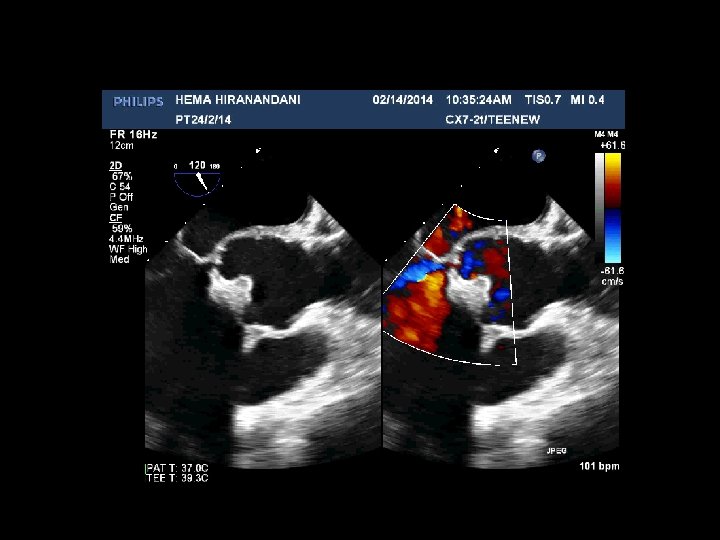

HEMA HIRANANDANI F 57 YRS • • • AVR BIO PROSTHETIC VALVE DEHISCENCE IE MULTIPLE VEGETATIONS ON BIO PRO VALVE AO ROOT ABSCESS SEVERE PARAVALVULAR AR RVSP= 37 mmhg

Hema Hirandani